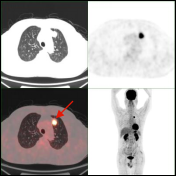

1.3早期发现和检出肿瘤,鉴别肿瘤良恶性

早期肺癌发现及鉴别:PET/CT显像示左肺上叶前段软组织灶(左图所示),糖代谢明显增高(SUVmax=15.3),经手术病理证实为肺腺癌。